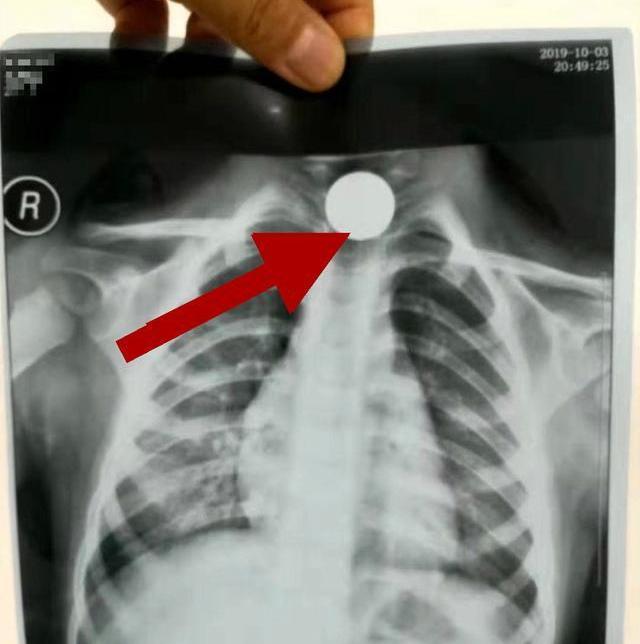

4歲女孩誤吞硬幣,醫生:做手術也取不出來了

一位4歲女童,誤將一枚五角的硬幣吞食,家長發現她哭鬧不止,捂著肚子,這才詢問得知女兒吞食的硬幣,嚇得爸媽連夜趕去了醫院治療。

醫生商量后決定手術取出硬幣,術前為了再次確認硬幣的位置,又讓家長帶去排了個片,誰知道醫生拿到片子以后卻搖搖頭說:“做手術也取不出來了。”

原來,這會硬幣已經由原來的食道轉移到了消化道,現在就算開刀動手術也沒辦法將硬幣取出來,只能通過孩子的消化功能自行排出體外。

這位寶寶是因為年紀偏大,食道以及發育較寬,加上五角硬幣不是特別大不會卡住不能動,在黏液的作用下進入到了消化道,可以隨著糞便一起排出,但是年紀小一點的寶寶可能就沒這么幸運了。